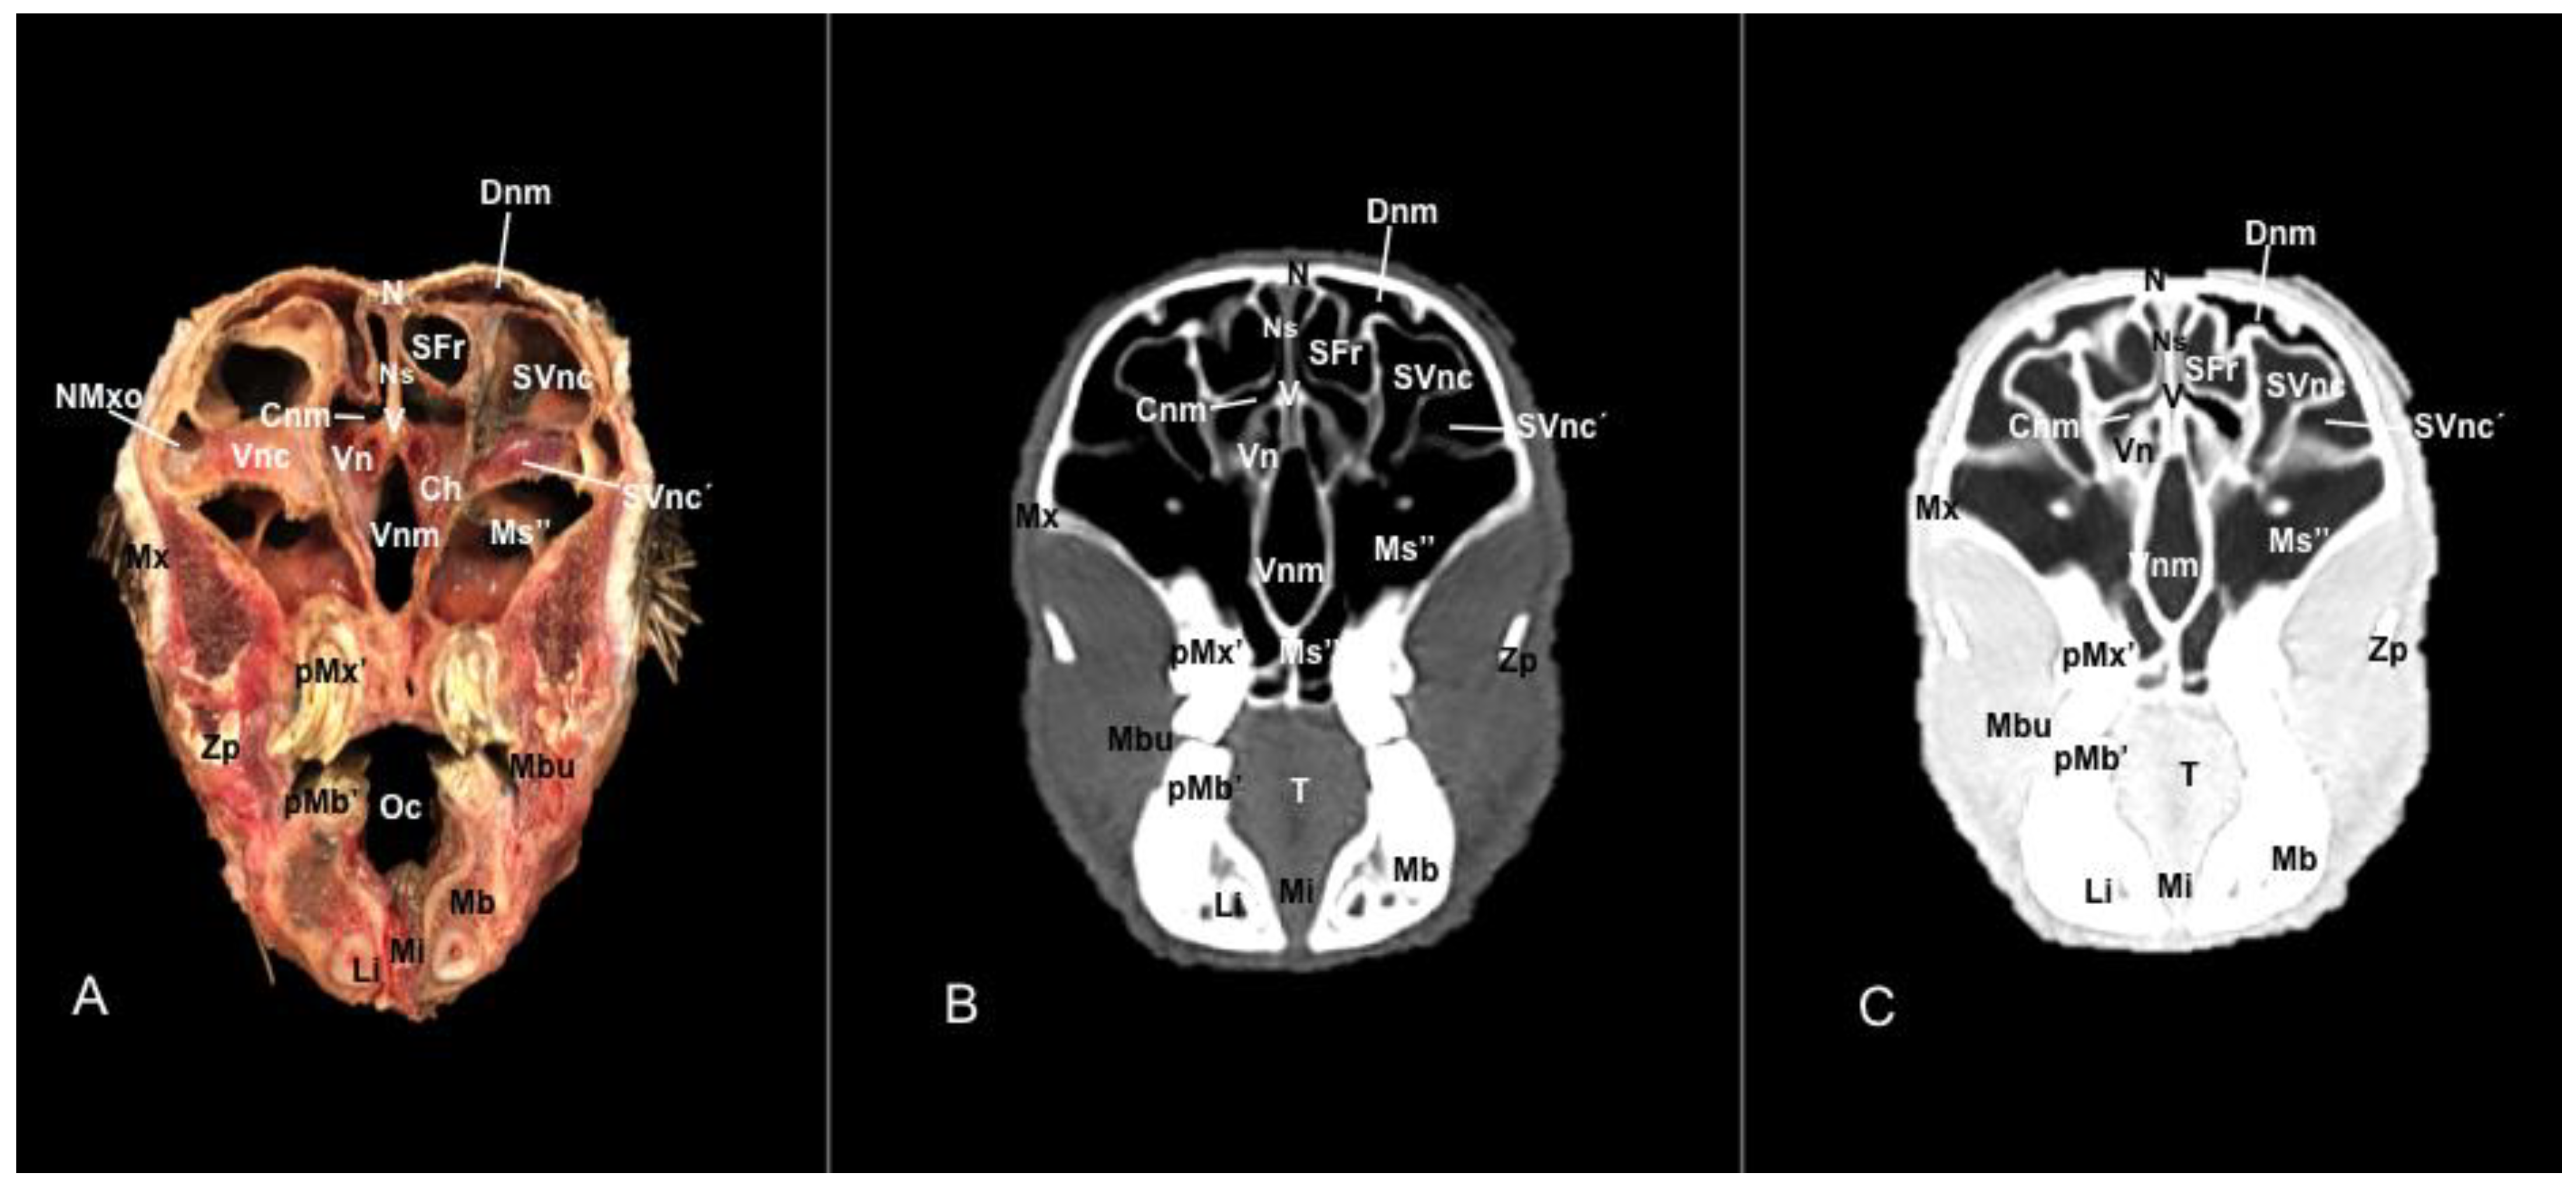

3.1. Anatomical Sections

3.2. Computed Tomography (CT)